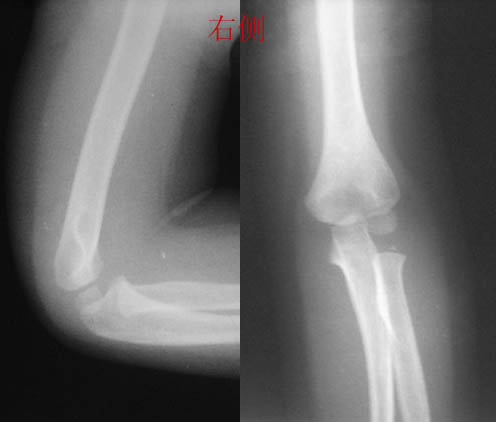

感谢大家的热烈讨论,应大家的要求,今天发右侧肘关节片,请大家继续讨论,讨论时对小儿肘关节二次骨化中心的多少、出现和闭合时间以及骺离骨折的判断和分型进行分析。

双侧对称,说明左侧肘关节骨质正常.